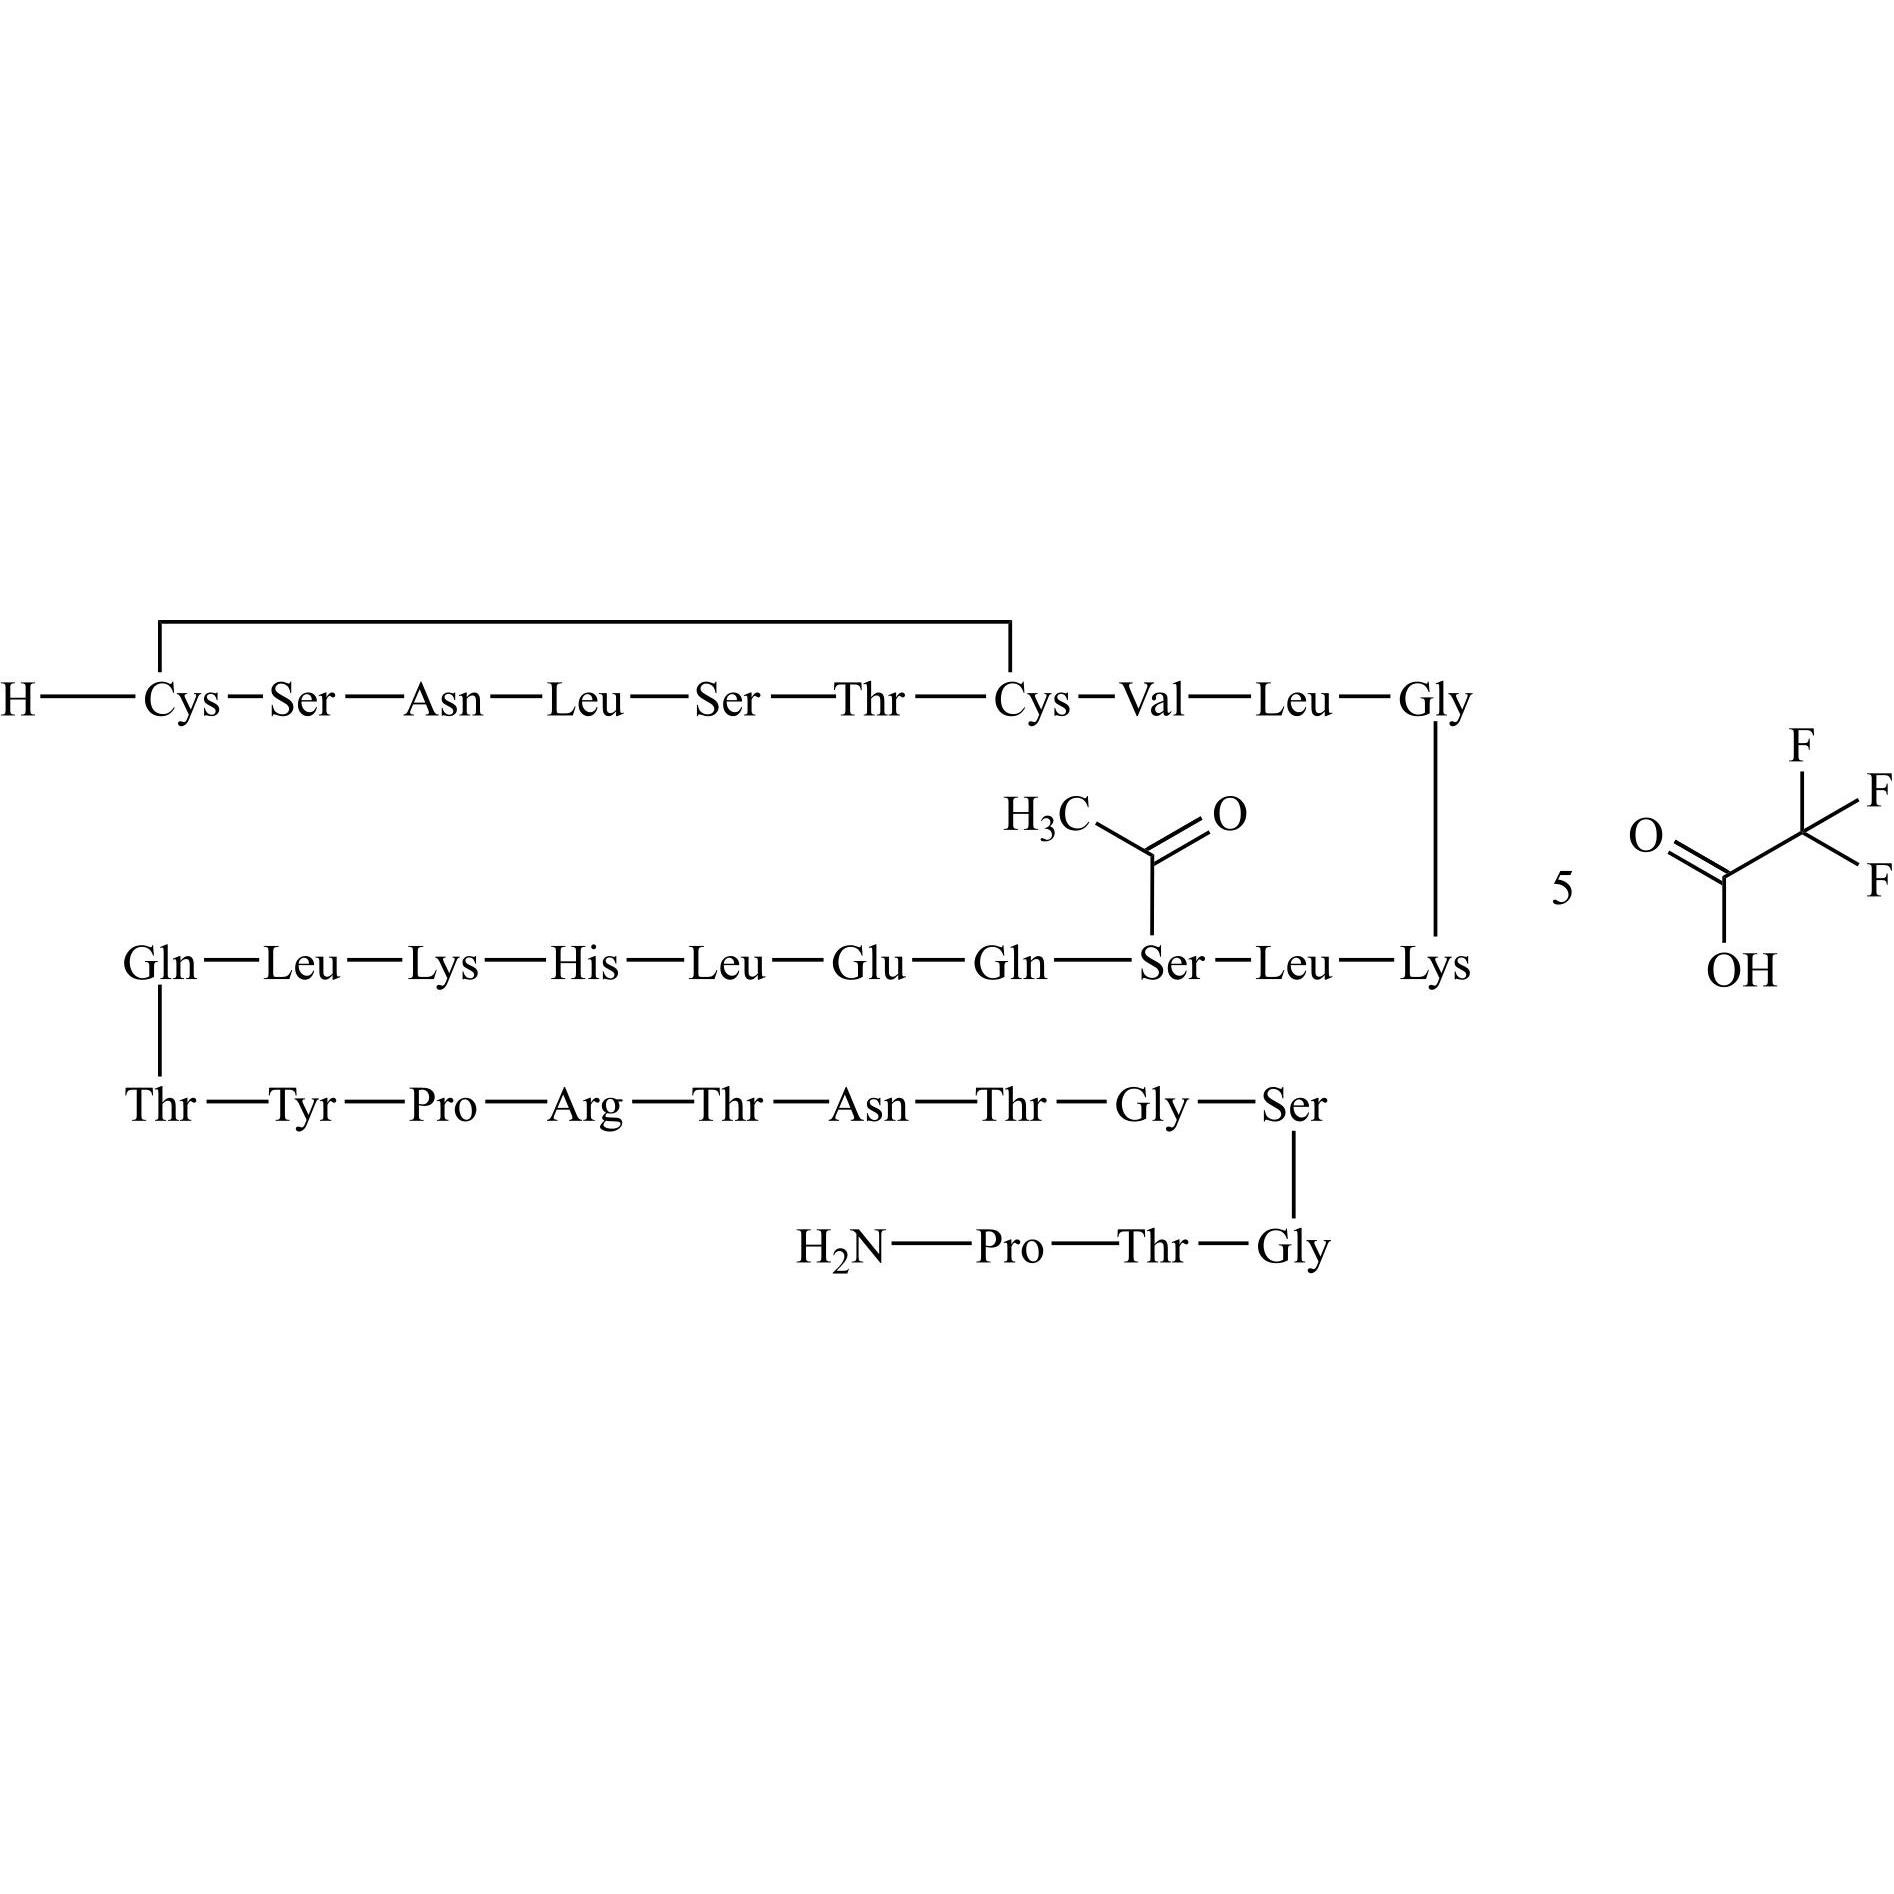

N-Acetyl-cys(1)-calcitonin Salmon Trifluoroacetic Acid

M.F.

M.W. 3474.94 ; 4(114.02)

CAT# AR-C05204

CAS# NA